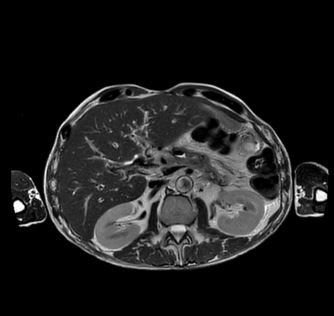

Beispiele von MRT-Abdomen Aufnahmen